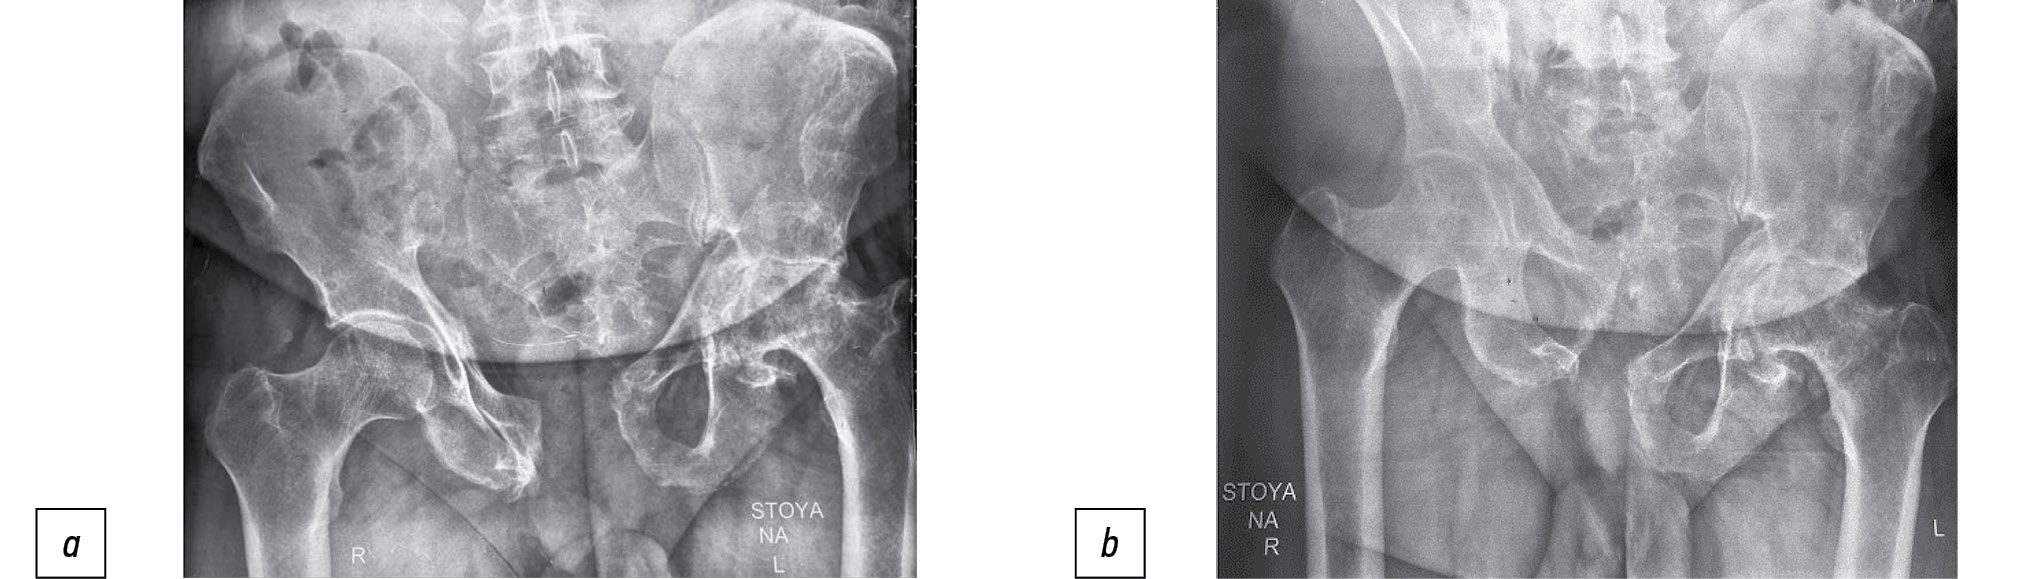

Moreover, all patients underwent computed tomography (CT) to clearly verify the pelvic ring damage, particularly, its posterior parts. In 15 (26%) patients, a solid three-dimensional model of the pelvic bones and lumbar spine was constructed for preoperative planning (Fig. 2).

Fig. 2. 3D model of pelvic and lumbar spine: а — front view; b — back view.